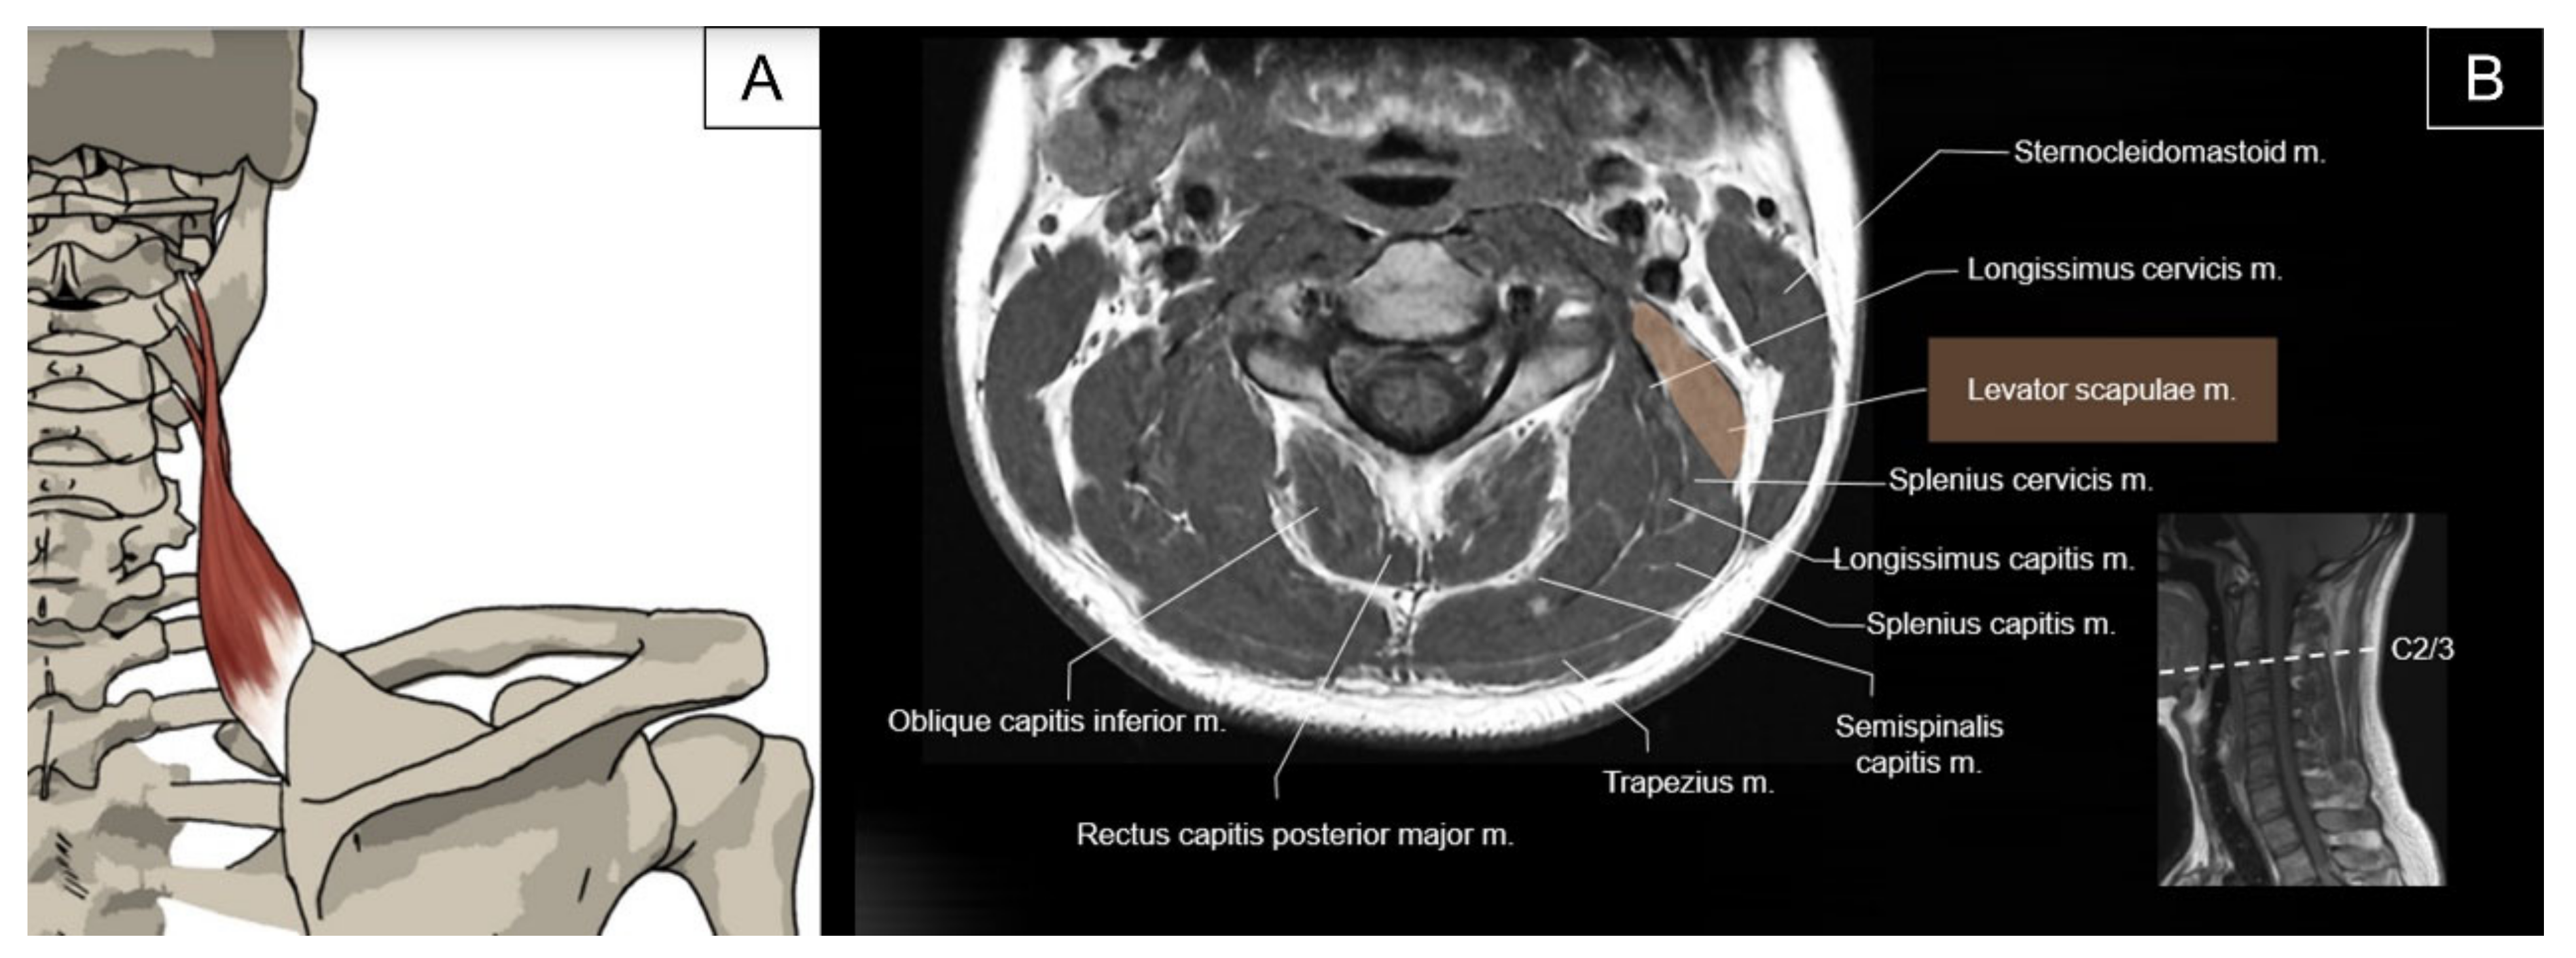

2.3. Levator Scapulae

2.3.1. Anatomy

2.3.2. Sonographic Scanning

2.3.3. Clinical Relevance